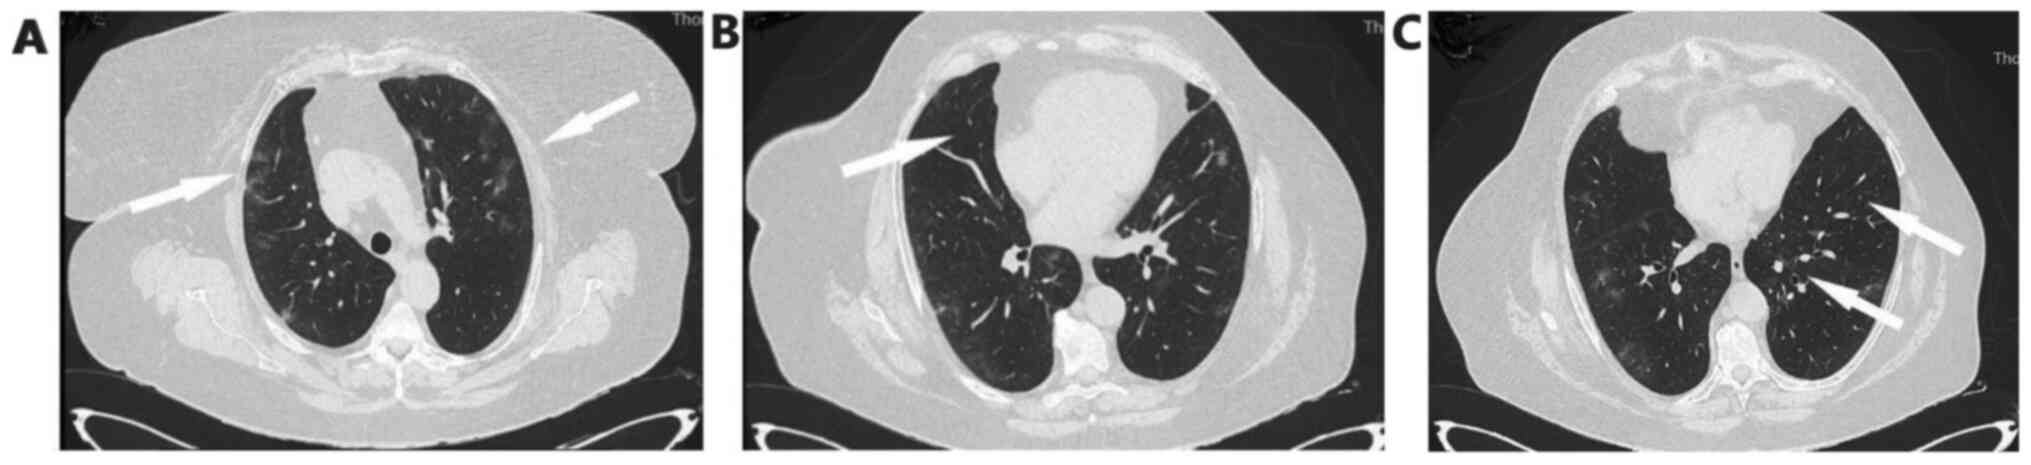

Arterial blood gas analysis showed pO2 52 mmHg, pCO2 32 mmHg, pH 7.53 and HCO3 26.7 mmol/l on room air. Chest X-Ray showed patchy diffuse infiltrates in both lungs mostly in the periphery of the left lung (Fig. 1A).

Figure 1

(A) On admission, chest X-ray shows bilateral lung infiltrates, mostly in the periphery of the left lung. (B) Chest X-ray on the 5th day shows worsening of infiltrates.

On the fifth day of hospitalization, fever reoccurred and the patient presented with worsening cough with green sputum, with reduction in partial pressure of oxygen, changes in findings from lung auscultation with rhonchi sounds found in all lung fields and worsening infiltrates on chest X-ray (Fig. 1B). The patient received oxygen with Venturi mask delivering 50% oxygen and intravenous piperacillin-tazobactam empirically. She underwent high resolution computed tomography of the chest showing bronchiectasis and nodular ground glass opacifications mostly with peripheral and subpleural distribution in both lungs (Fig. 2A-C).